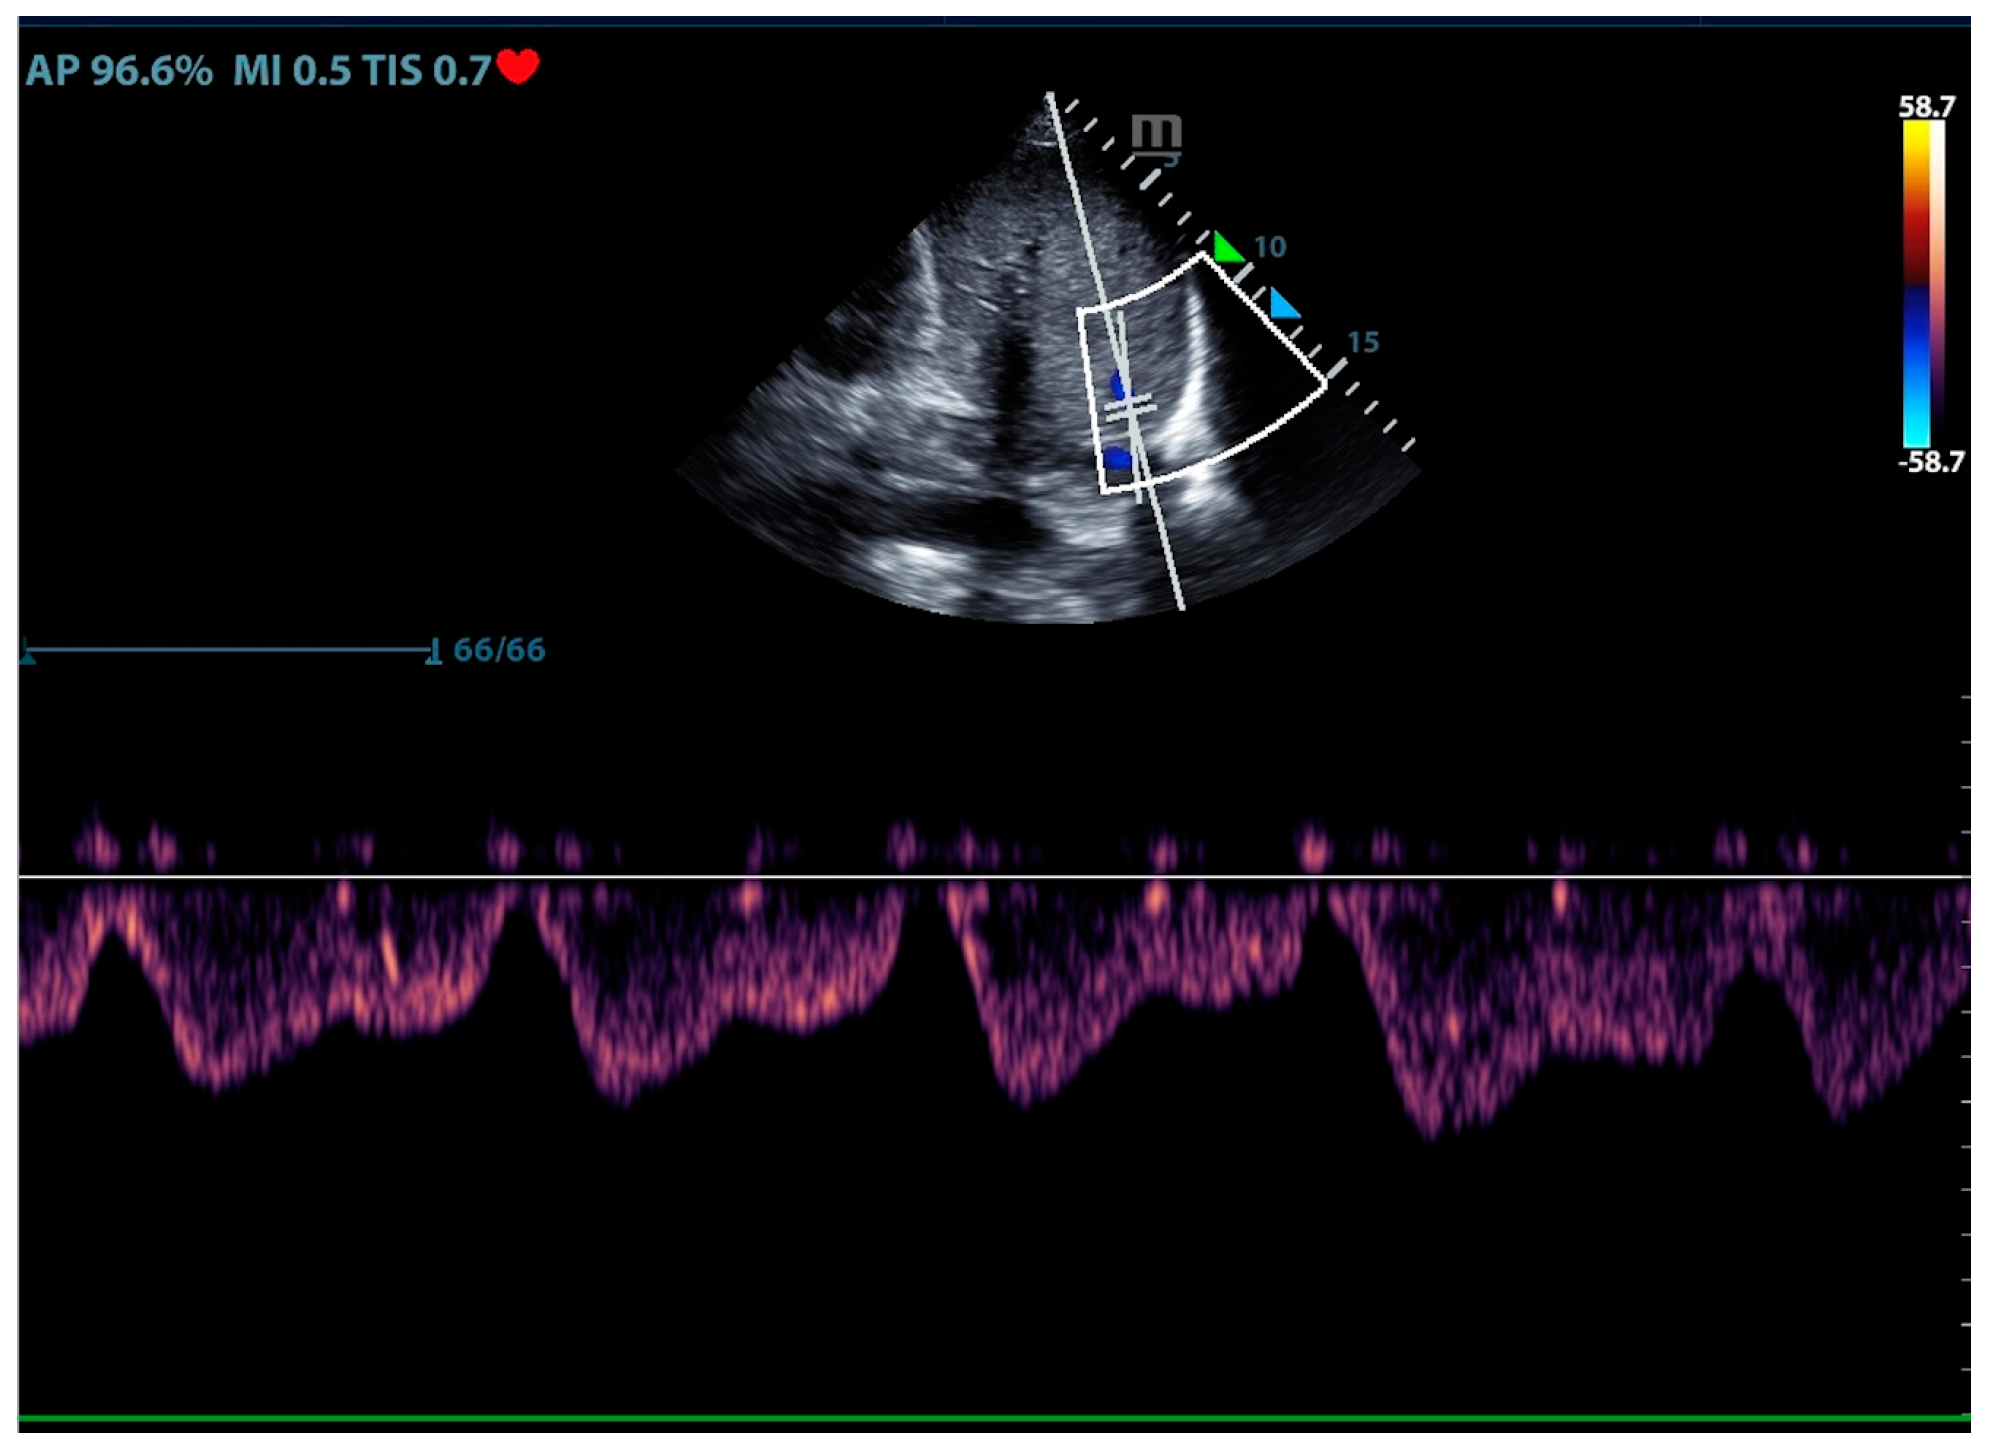

Physicians can assess pulmonary artery pressure quantitatively with point-of-care ultrasound. According to Bernoulli’s principle, the systolic pressure and diastolic pulmonary artery pressure can be estimated, respectively, by measuring the maximum regurgitation velocity of the tricuspid valve and the pulmonary valve. The maximum regurgitation velocity of the tricuspid valve (TVR Vmax) can be measured in the apical four-chamber view (Figure 6), and the maximum velocity of the pulmonary artery valve regurgitation (PVR Vmax) can be measured in the pulmonary artery long-axis view (Figure 7). Physicians can estimate pulmonary artery systolic pressure (PASP), diastolic pressure (PADP), and mean pulmonary artery pressure (mPAP) based on the ultrasound-measured TVR Vmax and PVR Vmax by the following formulas:

PASP = TVR Vmax2 + RAP(CVP)

PADP= PVR Vmax2 + RAP(CVP)

mPAP = 1/3 ∗ PASP + 2/3 ∗ PADP

Figure 6.

The ultrasound measurement of the maximum velocity of tricuspid valve regurgitation.

This can not only be used for the diagnosis of pulmonary hypertension but also for continuous and dynamic evaluation of pulmonary artery pressure [26]. It should be noted that the use of tricuspid regurgitation velocity to estimate pulmonary artery pressure with ultrasound Doppler has limitations. When the patient has severe tricuspid valve disease or severe right heart dysfunction, using the maximum tricuspid regurgitation velocity may underestimate the pulmonary artery pressure. Therefore, the evaluation of pulmonary hypertension should be combined with other ultrasound signs of the right ventricle, pulmonary artery, inferior vena cava, and right atrium.